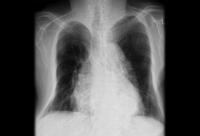

La radiografía de tórax muestra una marcada deformidad y pérdida de volumen del tórax óseo en un paciente con osteoporosis

BMJ Case Reports 2009; doi:10.1136/bcr.07.2008.0359. Copyright ©BMJ publishing group 2010